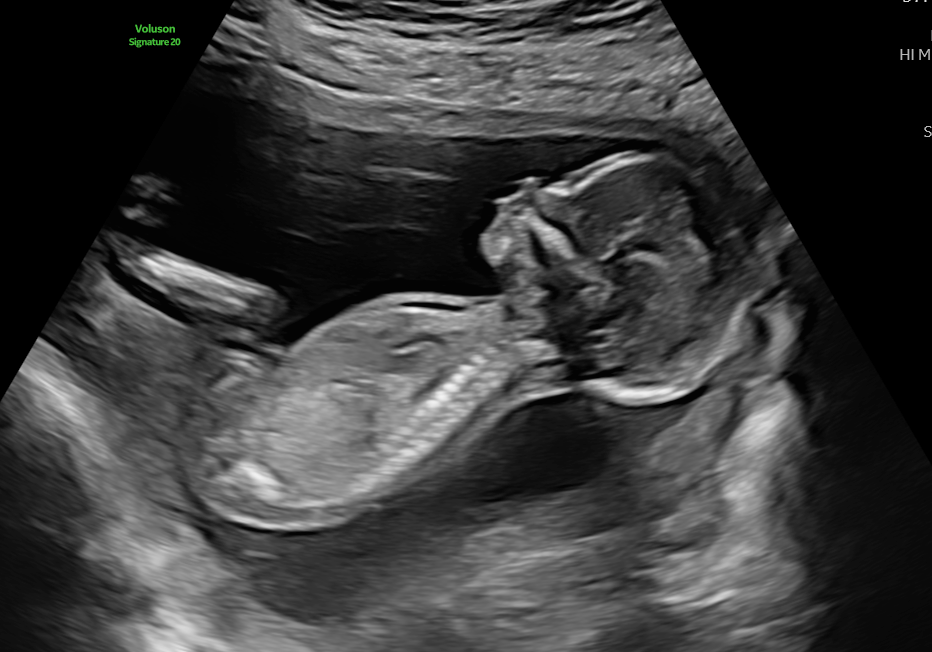

Anomaly pregnancy scan

Highly detailed ultrasound to assess your baby’s anatomy between 20–23 weeks.

Details of the anomaly scan

During the anomaly scan a detailed anatomical check is performed. Measurements are also taken to check the baby’s growth.

This examination is normally performed at 20 wks in the UK, it is to check the anatomy of the baby, to check the prescence of certain sructures and also to exclude pathology such as structural abnormalities which cannot be excluded from the 12 week scan. The heart is also examined in greater detail which again is note clearly visualised at the 12 wee scan.